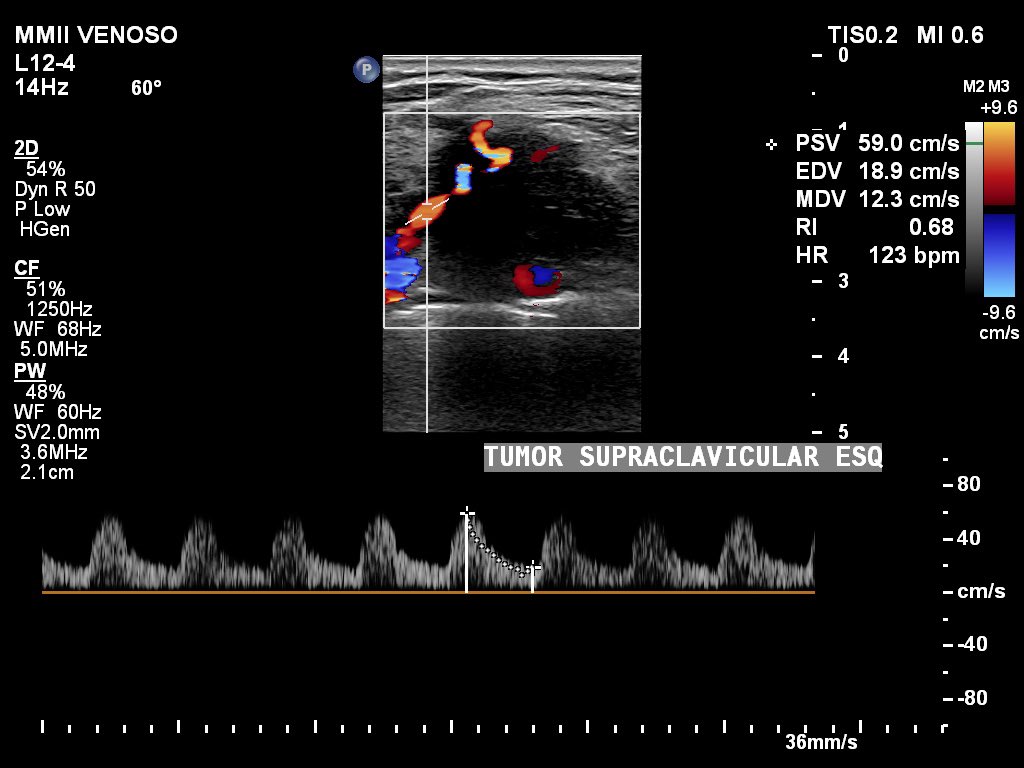

Troisier's sign (Charles Émile Troisier in 1889) = Virchow's sign (nodule) (in 1848) = metastatic L supraclavicular lymph node of a malignant tumor.

- Most common:

1. Gastric adenocarcinoma: 50 to 70%…

6. Breast cancer (L): (rare) < 3% (patient's case).

#vascularultrasound